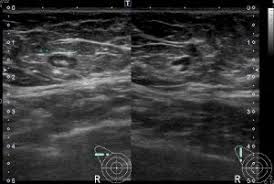

(3) 진단 방법

의료기관에서는 증상에 따라 초음파 검사로 멍울의 형태를 파악하고, 혈액검사로 감염 여부를 확인합니다. 필요시 조직검사를 통해 양성인지 악성인지 판단하게 됩니다.